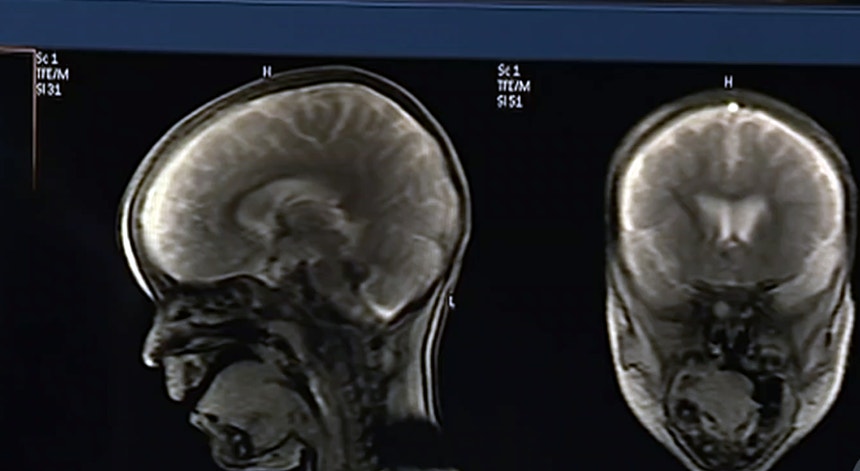

"Níveis alarmantes" de microplásticos no cérebro

Micro e nano-plásticos foram encontrados no cérebro humano e chegam a acumular-se mais do que nos rins e no fígado. Os cientistas norte-americanos responsáveis pelo estudo falam em resultados alarmantes.

Investigadores portugueses confirmam a tendência agravada por fatores ambientais e que pode justificar o aumento de doenças na infância e as doenças neuro-degenerativas, como Parkinson ou demências.